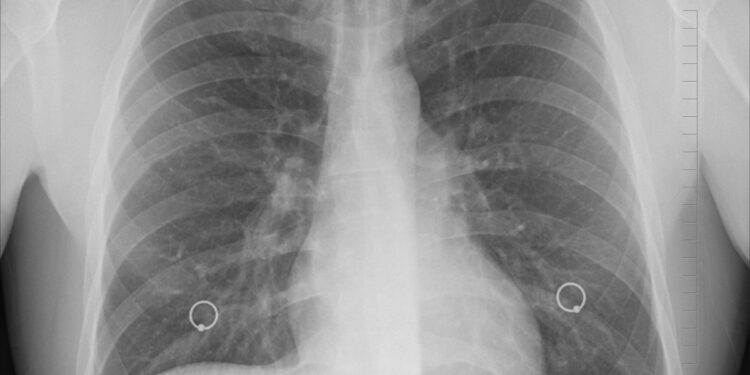

의협은 지난 16일 긴급 대책 간담회를 열고 “한의사의 X-ray 사용을 제도적으로 합법화하려는 위험천만하고 비상식적인 발상”이라며 “X-ray는 고도의 전문성과 해부학적 지식을 필요로 하는 의료장비로, 비전문가의 사용은 국민의 생명과 건강을 심각하게 위협한다”고 비판했다.

대한한의사협회(한의협)는 X-ray 기기 사용으로 기소된 한의사가 올해 초 항소심에서 무죄를 선고받은 뒤 X-ray를 적극적으로 활용하겠다고 선언했다. 수원지법은 지난 1월 X-ray 방식의 골밀도측정기를 환자 진료에 사용해 의료법 위반으로 기소된 한의사에 대한 항소심에서 원심판결과 같은 무죄를 선고한 바 있다.